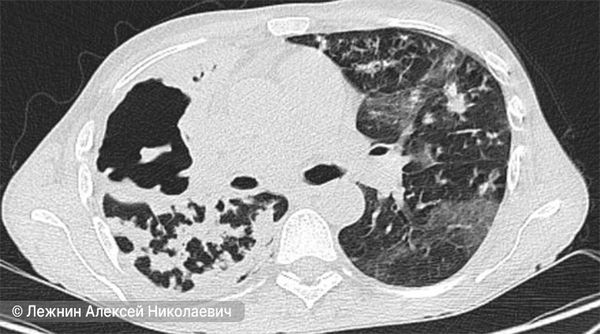

- Компьютерная томография (КТ) лёгких.

КТ-снимок лёгкого при казеозной пневмонии